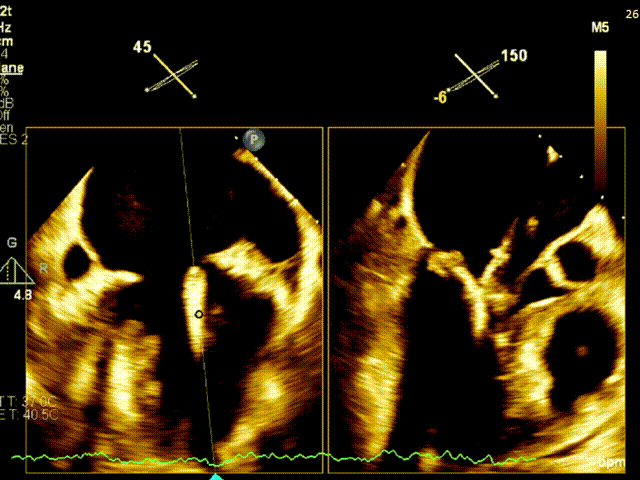

房间隔穿刺

手术过程

患者严重脊柱侧弯,仰卧抬足位于导管床,麻醉成功后。患者仰卧位,常规消毒、辅巾,穿刺左侧颈内静脉置管;穿刺左侧桡动脉测压。穿刺右侧股静胁,植入7F动脉鞘:放置PIG管于右房在房间隔切线位造影(延迟显像暴露LA),在Agilis-s可调弯鞠支持下TEE显示靠近房间隔,上下腔切面tenting不明显。考虑弯度欠佳,更换为Agilis-L可调弯鞘支持下房间隔穿刺鞘再次靠近房间隔,在TEE指导下 conquest pro钢丝连接电刀50/50J,成功穿刺进入左房,以Maverick 2.0*20mm球囊、QUANTUM 4.0*15mm、 QUANTUM 5.0*12mm球囊扩张房间隔,在extention连接钢丝下交换为房间隔穿刺鞘管进入左房,予super stiff置入左上肺静脉,于右股静脉沿super stiff推送MiaClap Guide Catheter G4于左房(因股静脉一右房-左房路径严重迂曲,SGC呈反方向)。于经食道超声指引下,推送XTW Clip Delivery System至二尖瓣左房面(inverted loading),食道超声确认12点钟方向推送至二尖瓣左室面,重新调整DC handle。使Clip Arm至1点钟方向。顺利捕捉二尖瓣前叶A1及后叶P1区域(覆盖脱垂区域),Gripper dowm后关闭Clip Arm 、 经食道超声评估二尖瓣返流量明显减少,确认有效夹持长度,确认瓣叶夹持牢固,释放瓣膜架。经食道超声再次评估二尖瓣返流量<1+,二尖瓣压差1.5mmHg,退出MitraClip系统。